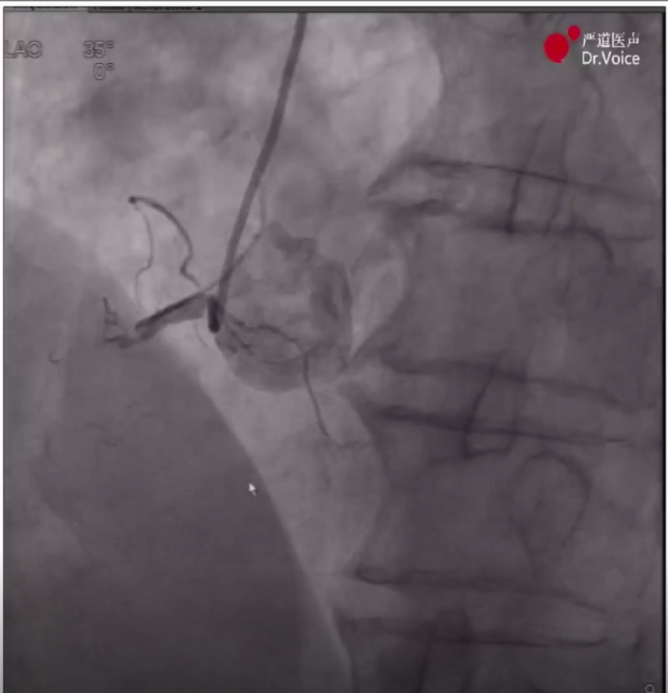

AGT技术将逆向导丝送入正向导管

5、送入Guidezilla辅助,采取AGT(Active Greeting Technique主动迎客技术),逆向Pilot200导丝顺利通过闭塞段,随后跟进逆向微导管进入正向指引导管内,将正向带2.0*15mm球囊的Pilot200导丝直接送入逆向微导管至右冠远端,随后进行常规球囊扩张并用IVUS明确血管腔内情况,在IVUS指导下完成支架植入,最后造影显示效果满意。